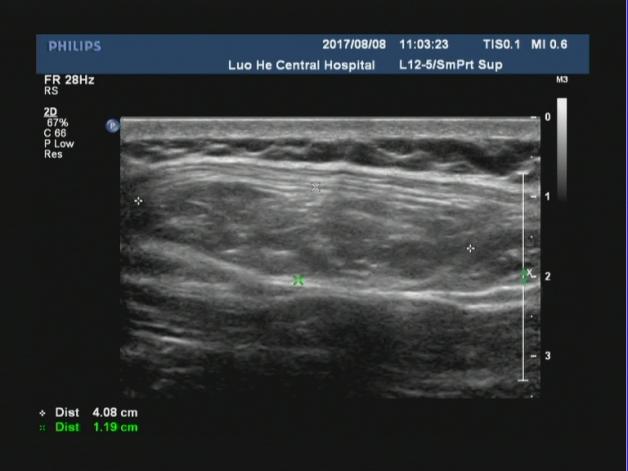

中年男性患者,腹部可见一巨大包块,位于开腹手术瘢痕处,从声像图上可以看出来,该包块直接位于腹部的皮下软组织后方,无肌肉层覆盖,而包块边界处可见肌肉层回声,并且包块内可见腹腔肠管回声,考虑符合腹壁的。

腹壁切口疝指临床体检可触及或影像学检查可显示的原手术切口下的腹壁缺损,是腹部外科手术后的常见并发症,常发生于年老体弱患者可伴或不伴腹壁包块,发病率通常为2%~11%。切口疝无法自愈,可引起患者不适或导致腹腔内容物绞窄。二维超声可直观了解疝环的大小、形态及深度,疝囊大小、位置,疝内容物及疝囊疝出和回纳途径。

对于切口疝二维超声扫描不仅能够清晰显示自皮肤表层到腹壁深层的解剖学全貌,还可直观显示切疝环的大 小、形态及深度,疝囊大小、位置及疝内容物。通过嘱患者用力咳嗽增加腹压或改变体位等方法,超声可实时动态显示疝囊由筋膜缺损处疝出以及回纳的过程。但随着腹壁外科的不断进展和疝修补技术的多样化,外科医师术前需要了解更具体的信息。以往研究认为二维灰阶超声可以检出所有切口疝。但当切口疝的缺损范围较大或存在多发性切口疝时,受小器官探头长度限制,二维灰阶超声存在测量数据明显偏小和病灶检出率明显降低等问题。因此我们可以采用现在新机器上的宽景成像技术,通过连续扫描与拼接图像,不仅可以在同一幅图像上显示较大范围的病灶并进行测量,还可显示周围相邻组织的情况。因此我们要会用、善用新软件,宽景成像不仅可对腹壁切口疝进行容积扫描,明显提高疝气病灶的检出率,客观显示整个切口疝的全貌,准确测量疝囊的大小,为临床医师对切口疝的分类提供准确数据;还可以显示二维超声所不能显示的冠状面图像,更准确地测量疝环,为临床医师选择疝修补术手术方式和决定补片大小提供具体精确的数据。